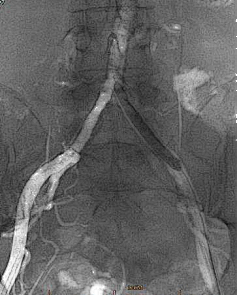

★ 造影评估

经腹主动脉造影如术中所见双侧髂动脉中-重度狭窄。

★ 管腔准备

引入Shockwave IVL M5(7.0×60mm)分别扩张双髂总动脉(将球囊充盈至4atm后,激发震波,在完成一组脉冲后,将球囊缓慢充盈至6atm并持续60秒)

★ 术后造影

左右髂外动脉狭窄明显好转